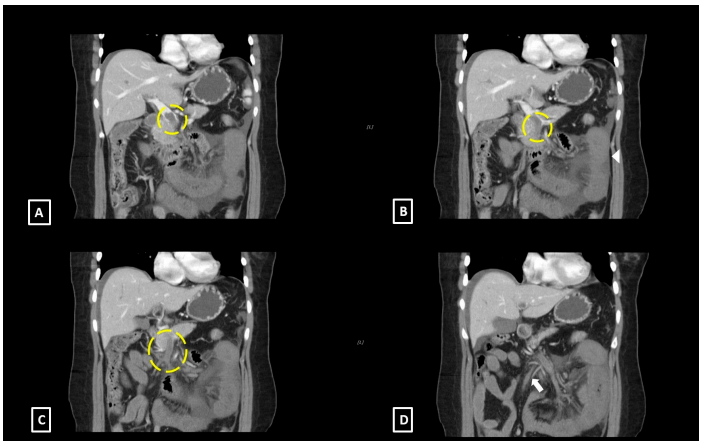

由于怀疑诊断为继发于SMV血栓形成的肠缺血,随后在静脉注射造影剂后进行了5 mm切片厚度的增强腹部和盆腔CT。CT图像显示门静脉主干内的充盈缺损向下延伸到SMV及其分支,以及SMV分支的静脉充血(图2)。其他发现包括小肠周壁增厚和低强化,以及相邻肠系膜脂肪内水肿改变。

图2. 腹部冠状位计算机断层扫描图像与静脉对比显示